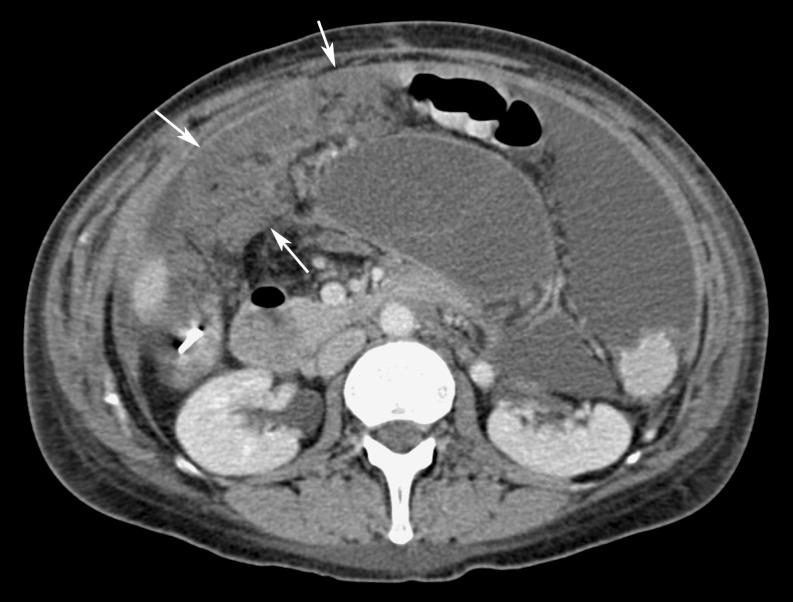

Omental cakes typically are associated with ovarian carcinoma, as this is the most common malignant aetiology. Nonetheless, numerous other neoplasms, as well as infectious and benign processes, can produce omental cakes. METHODS: A broader knowledge of the various causes of omental cakes is valuable diagnostically and to direct appropriate clinical management. RESULTS: We present a spectrum of both common and unusual aetiologies that demonstrate the variable computed tomographic appearances of omental cakes. CONCLUSION: The anatomy and embryology are discussed, as well as the importance of biopsy when the aetiology of omental cakes is uncertain.